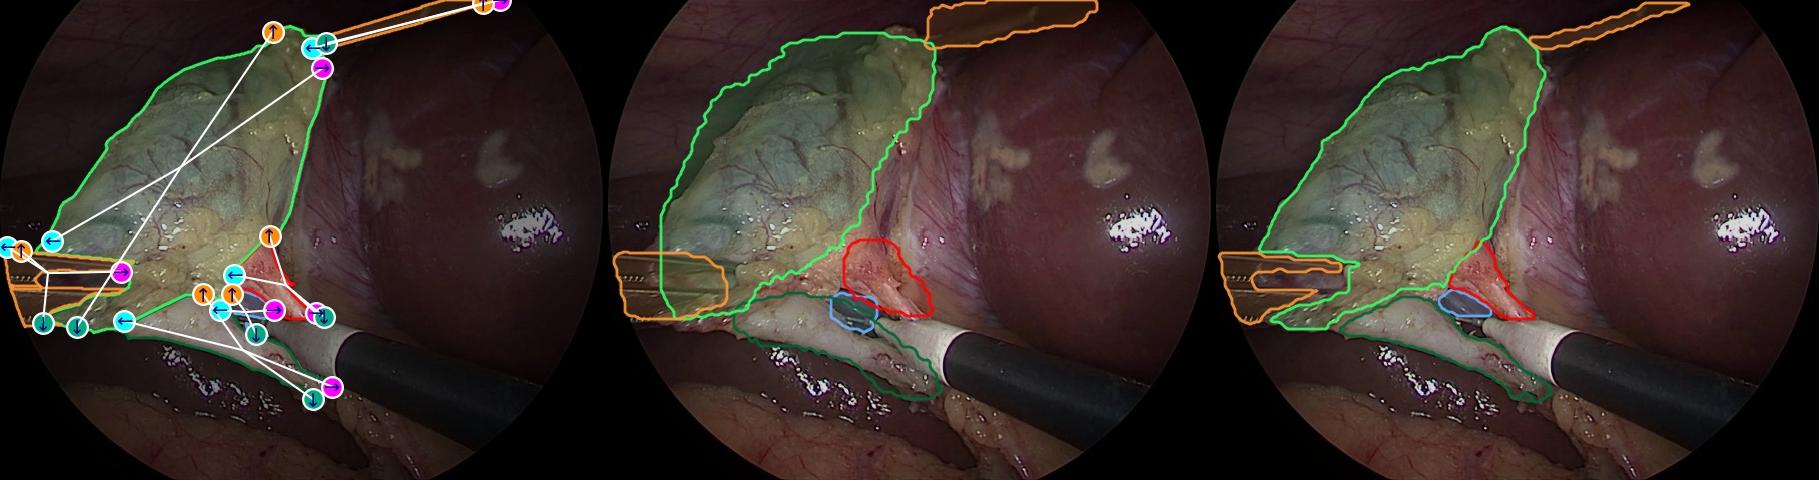

We present qualitative results in Fig. 6 and in the supplementary material. The Canvas proto-masks, generated from prompts alone without visual input, demonstrate that S4M has internalized how 4-points encode global shape, thereby improving the final masks. The resulting segmentations capture complex, highly concave structures more faithfully, with the 4-points anchoring multiple parts of the object boundary.

Shape Complexity. Not all structures are equally easy to segment. Simple, convex shapes can often be captured with minimal prompting, but highly concave or irregular ones remain difficult, as region- and box-based interaction provides little geometric constraint. These challenging shapes are common in medical imaging and drive up annotation cost, making robustness to geometric complexity a critical test for any interactive framework. We quantify complexity with a concavity index , normalized per dataset. Values near correspond to convex, regular shapes, while higher values indicate irregular and deeply indented outlines (examples in Fig. 7(a)). Fig. 7 shows performance stratified by concavity. Across both ultrasound and endoscopy, performance decreases as concavity grows, confirming the added difficulty of complex shapes. Yet S4M consistently narrows this gap: 4-point prompts maintain higher mIoU at all levels of concavity, with less performance drop in the higher concavity regimes. This indicates that explicitly encoding object geometry through four structured points makes the model more resilient to irregular boundaries than region-based prompting alone.